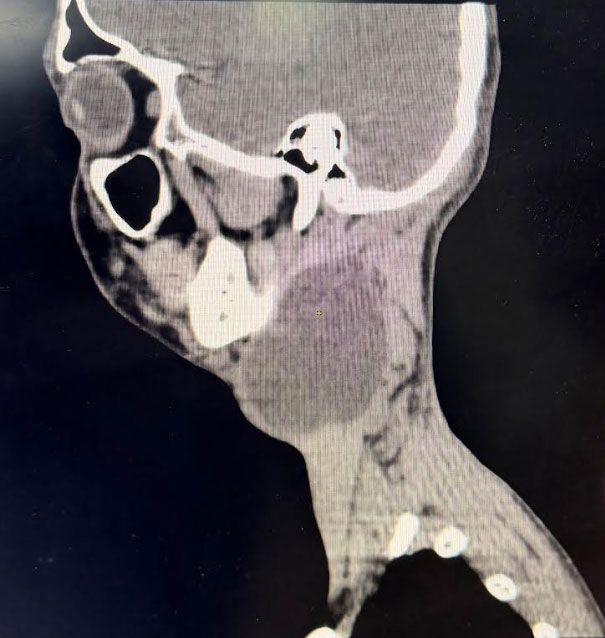

To evaluate the extent of the mass and plan the surgical approach, a CT scan of the neck was performed. The imaging provided clear, actionable data:

• Dimensions:Approximately 8 cm x 6 cm.

• Characteristics:A well-defined, unilocular cystic mass.

• Impact:Due to its significant size, the cyst was causing medial displacement of the surrounding neurovascular structures.